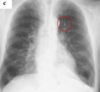

A

Consolidación alveolar

How well did you know this?